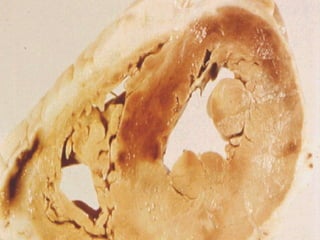

Daño a Órgano Blanco: Corazón:  Hipertensión maligna SNC:  Encefalopatía hipertensiva, Hemorragia cerebral, Infarto cerebral, Isquemia C. Transitoria Riñón:  Nefroesclerosis, Insuficiencia Renal Vasos:  Aneurismas, Disección aórtica

COMPLICACIONES ATEROSCLERÓTICAS: Cardiopatía Isquémica Enfermedad Vascular Cerebral Enfermedad Vascular Periférica

Daño a ÓrganoBlanco: Corazón: Hipertensión maligna SNC: Encefalopatía hipertensiva, Hemorragia cerebral, Infarto cerebral, Isquemia C. Transitoria Riñón: Nefroesclerosis, Insuficiencia Renal Vasos: Aneurismas, Disección aórtica

COMPLICACIONES ATEROSCLERÓTICAS: CardiopatíaIsquémica Enfermedad Vascular Cerebral Enfermedad Vascular Periférica